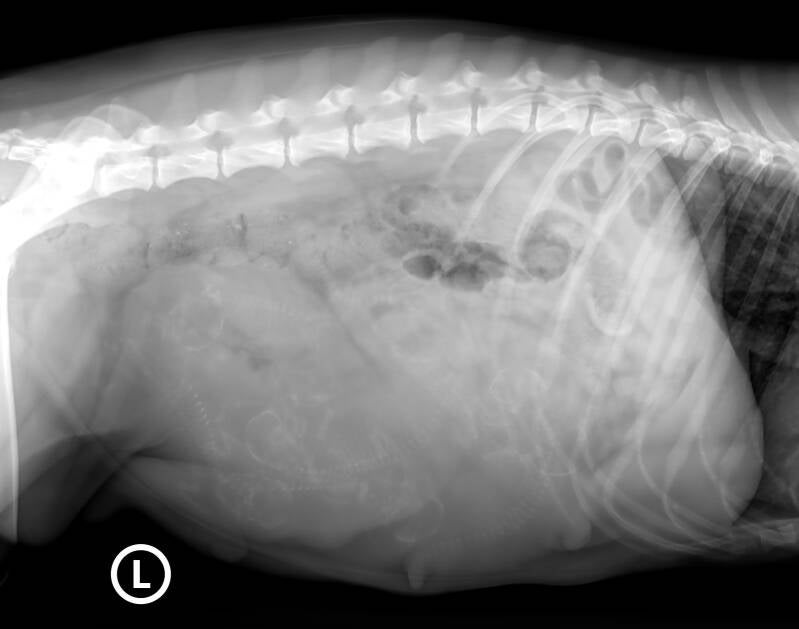

🍀🐾🐾Heute waren wir beim Röntgen🐾🐾🍀

Es werden 6 bis 7 Welpen